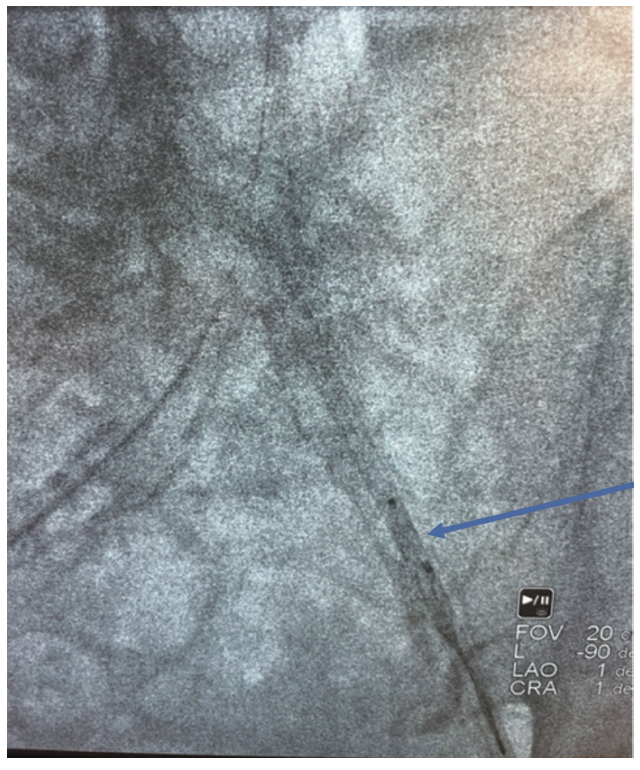

The patient was brought to the cath lab. Under ultrasound guidance and with micropuncture technique, a 6 French (Fr) sheath was inserted in the right femoral artery and an 8 Fr sheath was placed in the left femoral artery. The left arterial access was “pre-closed” with the Perclose device (Abbott Vascular). The patient was appropriately anticoagulated. A 5 Fr balloon wedge pressure catheter was inserted into the right femoral artery. The balloon was inflated to assist with capturing the AVP2. The left femoral artery access was upsized to a 10 Fr Pinnacle 25 cm sheath (Terumo). A Judkins right (JR) 4 coronary guide catheter was advanced over a wire. A 6 Fr EN Snare device (Merit Medical) was advanced through the guide catheter and after multiple attempts, captured the AVP2. The EN Snare was retracted into the guide catheter (Figure 5) and the catheter system was removed (Figure 6). Digital subtraction of the abdominal aorta was performed, noting no evidence of a mobile clot, dissection, or perforation of the iliac artery. The balloon catheter and wires were removed, and the accesses were actively closed. Post procedure, the patient was taken to the intensive care unit for further monitoring.